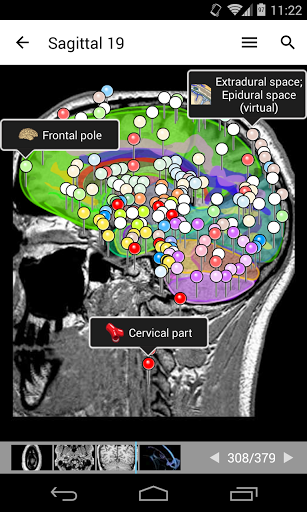

e-Anatomy memiliki lebih dari 26.000 gambar yang berisi serangkaian gambar dalam tampilan aksial, koronal, dan sagital serta radiografi, angiografi, gambar diseksi, bagan anatomi, dan ilustrasi. Semua gambar medis diberi label dengan cermat, lebih dari 967.000 label tersedia dalam 12 bahasa termasuk Terminologia Anatomica Latin.

- Gulir set gambar dengan menyeret jari Anda

- Perbesar dan perkecil

- Ketuk label untuk menampilkan struktur anatomi